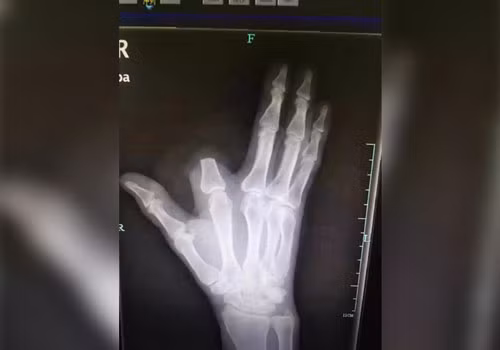

Càng nghĩ càng hoảng hốt, ông vội vàng cầm rìu chặt bỏ ngón tay còn in dấu răng của con vật đáng sợ.

Tiếp đến, ông nhanh chóng lấy vải quấn chặt tay và băng đoạn đường 80 km đến Hàng Châu, thành thị lớn nhất gần đó, để tìm bác sĩ cứu chữa vết thương.

Tuy nhiên, vì cho rằng ngón tay bị đứt đã nhiễm độc tính nên ông đã vứt lại trong rừng. Chuyện đến nước này, các bác sĩ tại Bệnh viện Y học Cổ truyền Hàng Châu cũng đành lắc đầu chịu thua vì không có cách nào nối liền ngón tay với bàn tay được nữa.

Yuan Chengda, một bác sĩ khác tại Bệnh viện Y học Cổ truyền Hàng Châu, bày tỏ sự tiếc nuối khi ngón tay của ông Zhang không thể gắn lại với cơ thể được nữa.